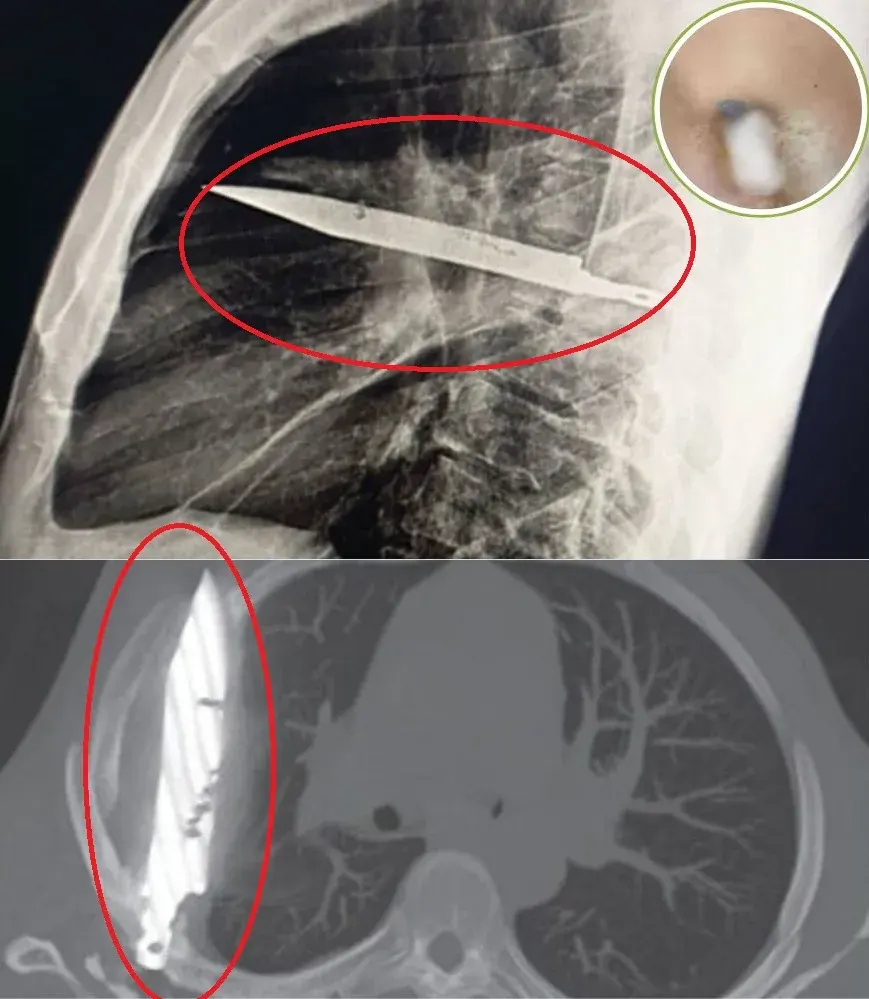

ภาพเอกซเรย์ที่ทำเอาทุกคนอึ้ง

คุณหมอเลยตัดสินใจส่งเอกซเรย์ พอผลออกมาเท่านั้นแหละครับ…ทั้งทีมแพทย์ช็อกแทบพูดไม่ออก เพราะเห็นวัตถุแปลกปลอมขนาดใหญ่ฝังอยู่บริเวณหน้าอกด้านขวา และมันคือ “ใบมีดเล่มโต” ชัด ๆ

ใบมีดทะลุผ่านสะบักขวา แต่ที่โคตรมหัศจรรย์คือมันดัน “เลี่ยง” อวัยวะสำคัญอย่างหัวใจ ปอด และเส้นเลือดใหญ่ไปได้อย่างเหลือเชื่อ เรียกว่าหากตอนนั้นมันเฉไปอีกนิดเดียว เขาคงตายไปแล้วตั้งแต่ 8 ปีก่อนแล้วครับ